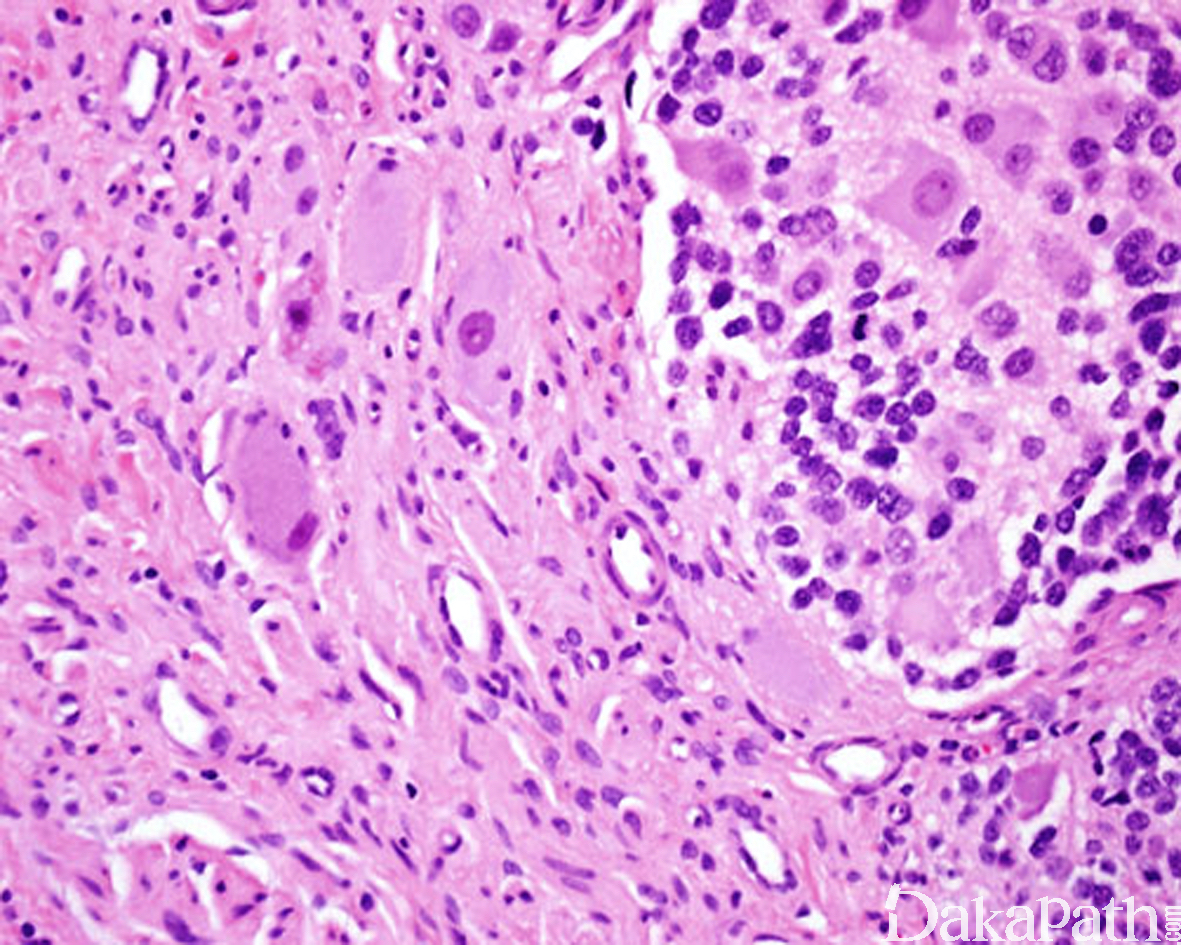

混合型节细胞神经母细胞瘤,由界限相对清楚的神经母细胞肿瘤巢与丰富的节细胞神经瘤性成分组成,后者占肿瘤的 50%以上,神经母细胞肿瘤巢由不同分化阶段的神经母细胞(以分化型神经母细胞为主)和丰富的神经毡型间质组成;

结节型节细胞神经母细胞瘤:大体上能看到 1 个或多个神经母细胞性结节,通常伴出血或坏死,镜下见神经母细胞性结节与节细胞神经瘤成分之间有清晰的分界线。